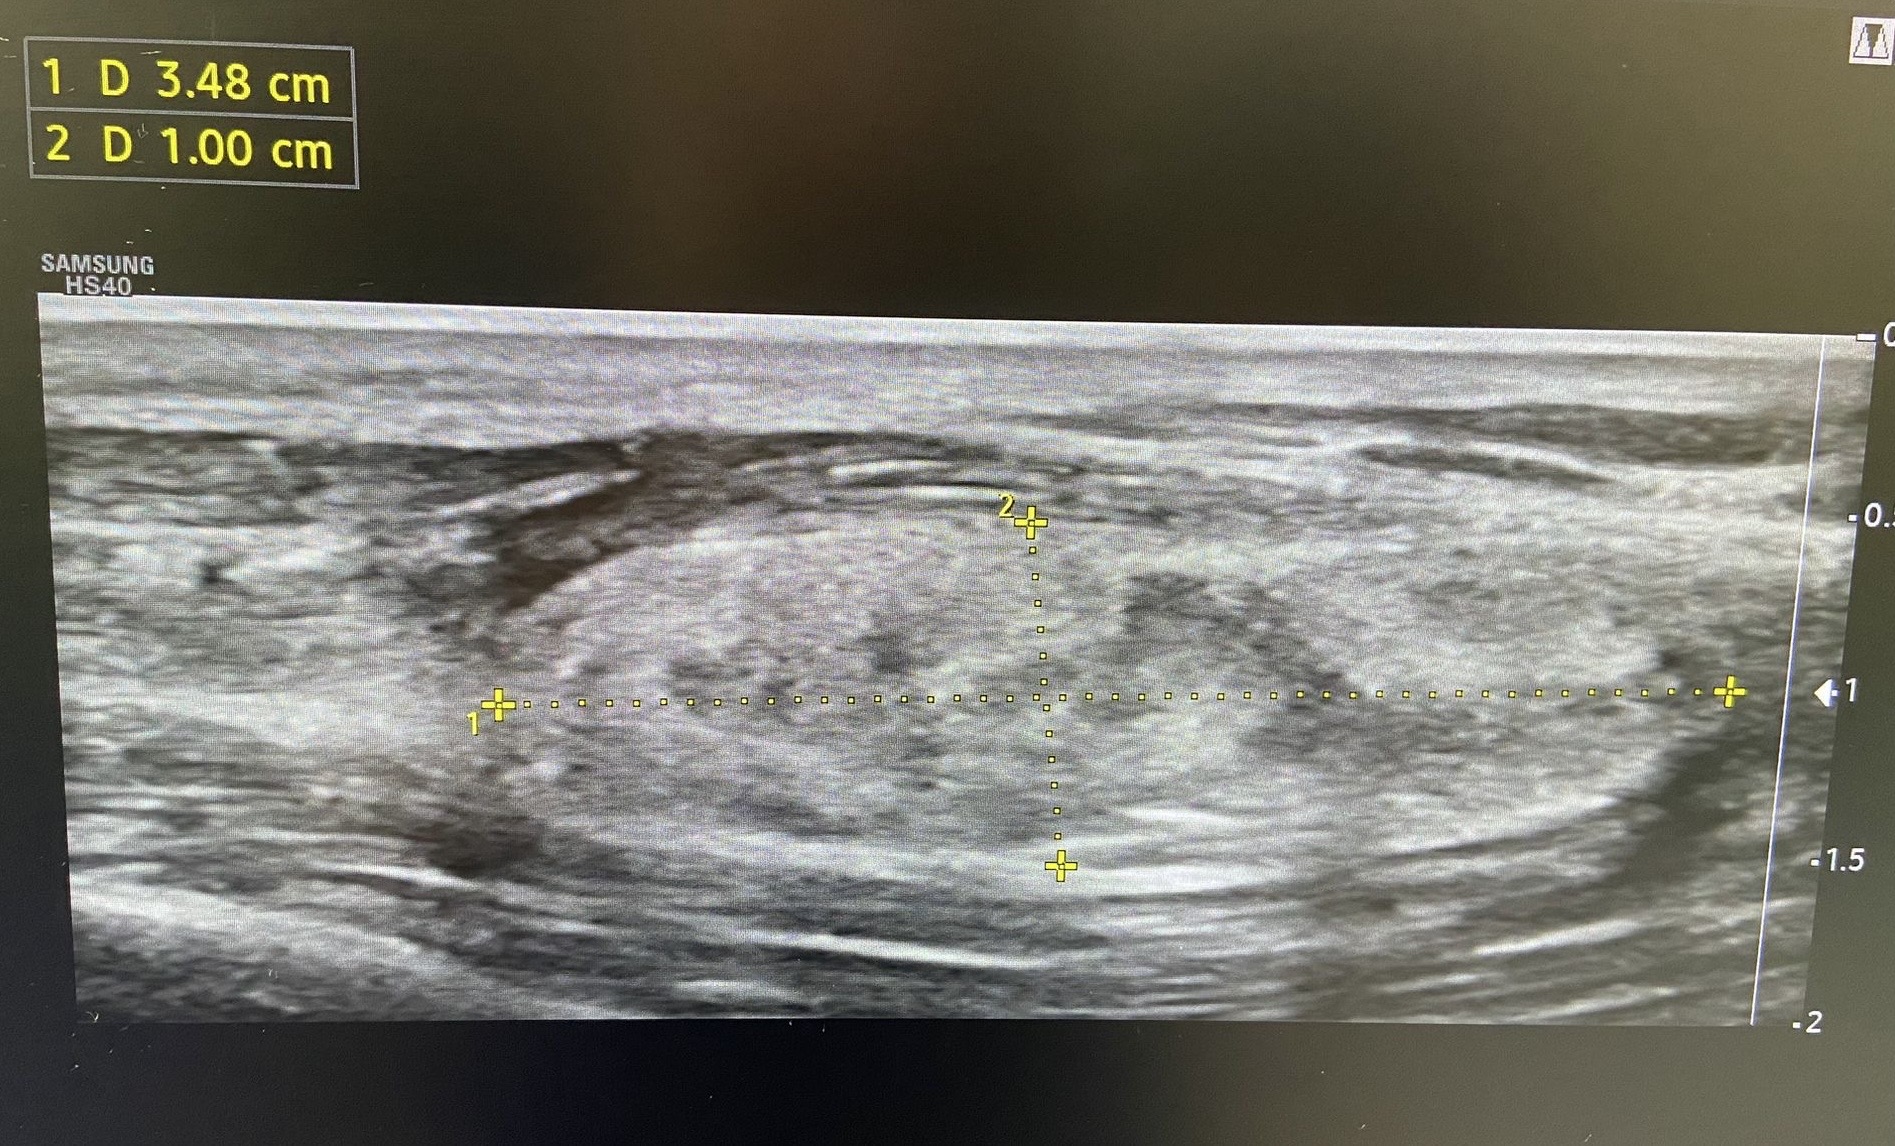

Ecografía clínica en consulta: Se observa una lesión bilobulada, isoecoica respecto a la grasa, levemente heterogénea, de bordes bien definidos, de aproximadamente 33 × 11 × 18 mm. En el estudio Doppler color se identifican estructuras vasculares en su interior.